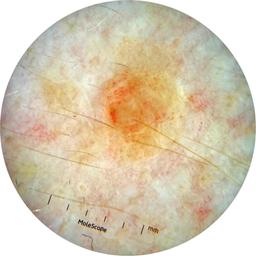

ISIC_3176953

Information

2135 x 2135

Clinical

Field Value

acquisition_day 410

age_approx 40

anatom_site_1 Head and neck

anatom_site_general head/neck

concomitant_biopsy False

diagnosis_1 Malignant

diagnosis_2 Malignant adnexal epithelial proliferations - Follicular

diagnosis_3 Basal cell carcinoma

diagnosis_confirm_type single image expert consensus

family_hx_mm False

fitzpatrick_skin_type I

image_manipulation instrument only

image_type dermoscopic

lesion_id IL_4059380

patient_id IP_8700330

personal_hx_mm True

sex female